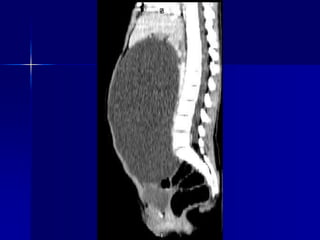

Пухлина надзвичайно варіабельна в розмірах: від

розміру горошини до заповнення нею черевної

порожнини. У 95 % вона локалізується у тілі

Консервативна міомектомія

Гігантська міома матки